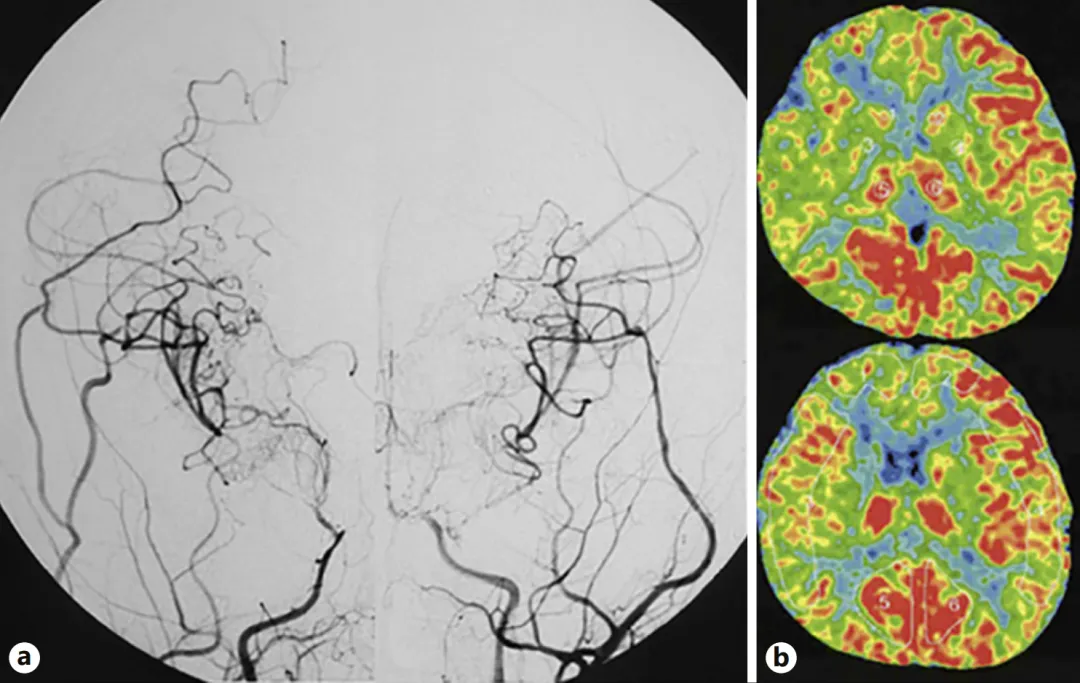

图a:第二次手术半年后,双侧颈内动脉血管造影显示侧支血管网络发育良好,基底烟雾血管消退。

图b:双侧脑血流显示有所改善。